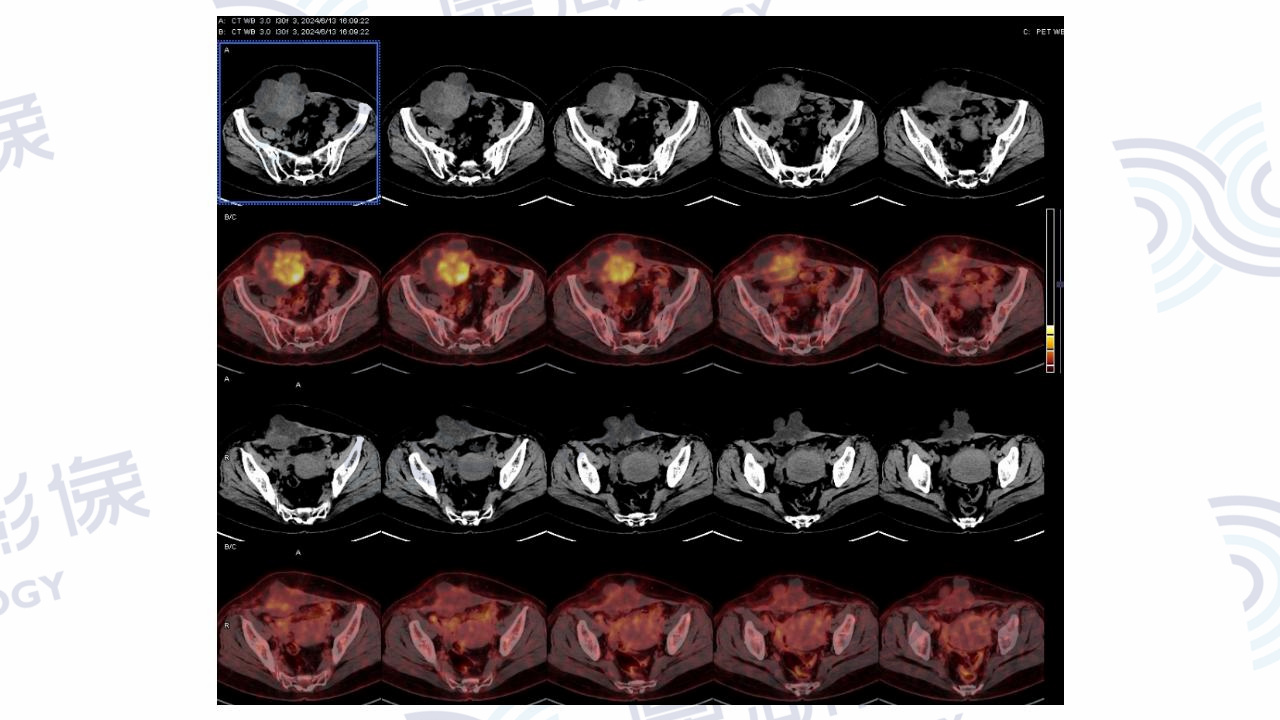

腹壁透明细胞癌

主诉:发现右下腹包块多年,自觉包块增大1年。

患者于一年前出现腹痛,查体提示右下腹包块,未行治疗。一年后复查腹部肿块增大,肿瘤标志物未见异常。剖宫产及腰椎间盘突出手术史。